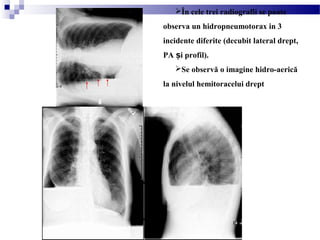

În cele trei radiografii se poate

observa un hidropneumotorax in 3

incidente diferite (decubit lateral drept,

PA i profil).ș

Se observă o imagine hidro-aerică

la nivelul hemitoracelui drept

(pneumotorax spontan secundar la un pacient cu

fibroză chistică, se observă un hidropneumotorax

drept cu bron iectazii chistice bilaterale)ș

Radiografie toracică, înciden ă PAț